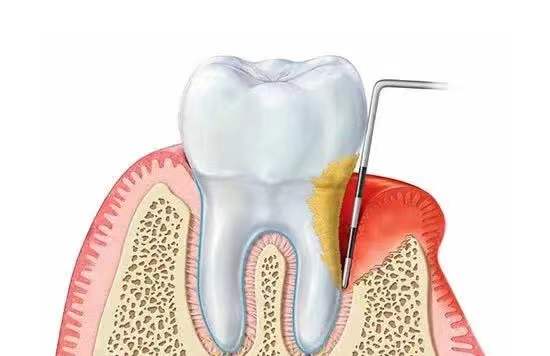

是否需要植骨取决于牙槽骨的条件,缺牙多年或本身有严重的牙周病等情况容易导致牙槽骨萎缩。牙槽骨吸收使牙齿根基变浅,牙齿变长,随着骨吸收现象的日趋加剧,牙齿自然也就脱落得更多了。

很多老年人缺牙不补,久而久之引发牙周炎症,一旦发展到重度,会造成牙龈萎缩和牙槽骨损伤;或者因为骨质疏松而骨量不足。

骨质的“高度”、“宽度”和“密度”都会直接影响植牙的成败。种树需要土壤,树苗才能成长,种植牙也需要足够健康的骨组织,手术才能成功并且保证种植牙的长久使用。

若牙槽骨有缺损却没有进行植骨可能导致种植体不稳,易损伤牙神经、易感染甚至种植牙发炎脱落等。